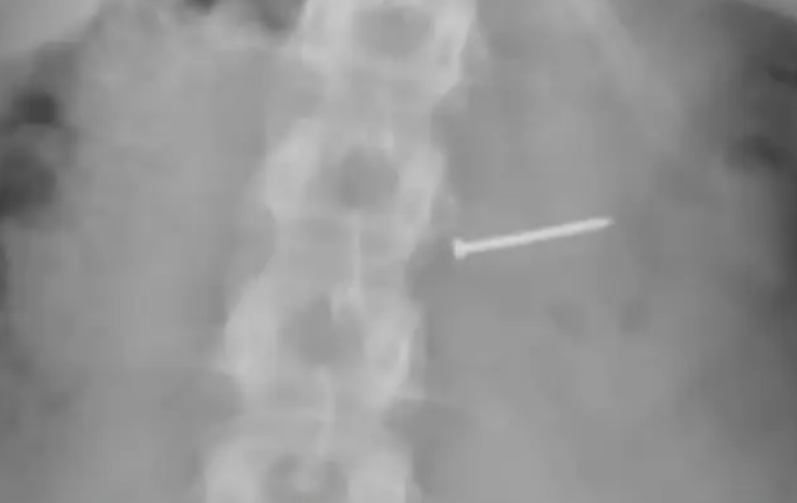

وبعد نقلها إلى المستشفى، أظهرت الفحوصات بالأشعة أنها لم تبتلع مسمارا واحدا فقط، بل أيضا شظايا معدنية أخرى استقرت داخل أمعائها، ما استدعى تدخلا جراحيا عاجلا لاستخراجها. لكن المضاعفات لم تتوقف عند هذا الحد، إذ أصيبت لاحقا بجلطة دموية أدت إلى مضاعفات صحية خطيرة أثرت بشكل دائم على جهازها التناسلي.

المسمار داخل جسد السيدة!